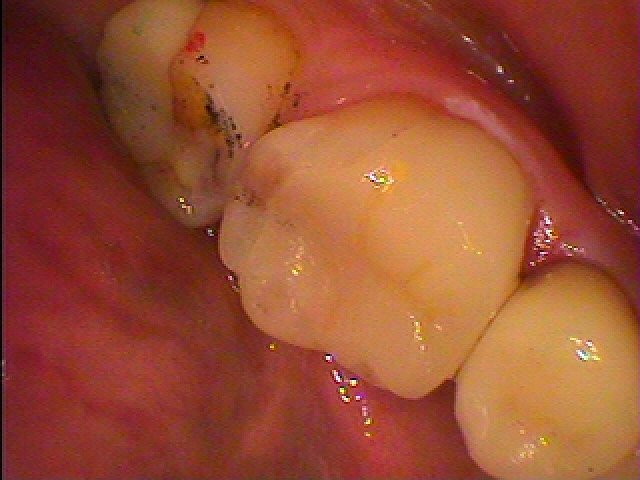

左下6番

この銀歯が虫歯ですので麻酔をかけて外していきます

銀歯を外していきました

虫歯だらけです